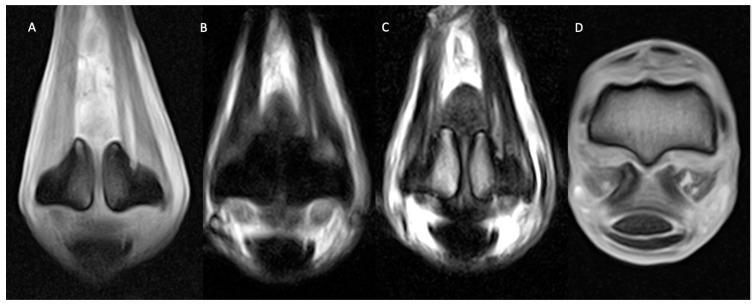

使用站立式磁共振成像对341匹马的掌指关节和跖趾关节区域病变分布情况的研究

Lesion Distribution in the Metacarpophalangeal and Metatarsophalangeal Region of 341 Horses Using Standing Magnetic Resonance Imaging.

Pain localised to the metacarpophalangeal (MCP) and metatarsophalangeal (MTP) region represents a frequent cause of lameness in sport horses, and standing magnetic resonance imaging (MRI) of these regions is increasingly being acquired. This multicentre retrospective study describes the ranges of abnormalities identified on standing MRI of the MCP/MTP region and compares patterns of abnormalities between forelimbs, hindlimbs and different sports disciplines. In total, 341 MRI reports were reviewed. Subchondral bone plate irregularities, condylar and proximal phalanx pathologies were frequently identified with subchondral bone defect, sclerosis and increased intensity on STIR images often described. Medial pathology was frequently identified in the forelimbs, and more lateral pathology was reported in the hindlimbs, which could potentially reflect differences in the loading patterns. Significant differences in MRI findings were found between different sports activities, with MCP/MTP bone pathology occurring more frequently in MRI reports from race and endurance horses and MCP/MTP soft tissue injuries being reported more frequently in dressage and show-jumping horses, particularly in the suspensory apparatus, including the distal sesamoidean ligaments. The findings of this study identify patterns of MCP/MTP abnormalities detected using standing MRI, with differences seen between forelimbs and hindlimbs and between different sports disciplines.

摘要

局限于掌指关节(MCP)和跖趾关节(MTP)区域的疼痛是运动马匹跛行的常见原因,这些区域的站立位磁共振成像(MRI)检查越来越普遍。这项多中心回顾性研究描述了在MCP/MTP区域站立位MRI上发现的异常范围,并比较了前肢、后肢以及不同运动项目之间的异常模式。总共审查了341份MRI报告。经常发现软骨下骨板不规则、髁和近节指骨病变,并常描述有软骨下骨缺损、硬化以及短T1反转恢复(STIR)序列图像上信号增强。前肢常发现内侧病变,后肢则更多报告外侧病变,这可能反映了负荷模式的差异。不同体育活动的MRI表现存在显著差异,MCP/MTP骨病变在赛马和耐力赛马的MRI报告中更常见,而MCP/MTP软组织损伤在盛装舞步和场地障碍赛马中报告更频繁,尤其是在悬韧带装置,包括远籽骨韧带。本研究结果确定了使用站立位MRI检测到的MCP/MTP异常模式,前肢和后肢以及不同体育项目之间存在差异。